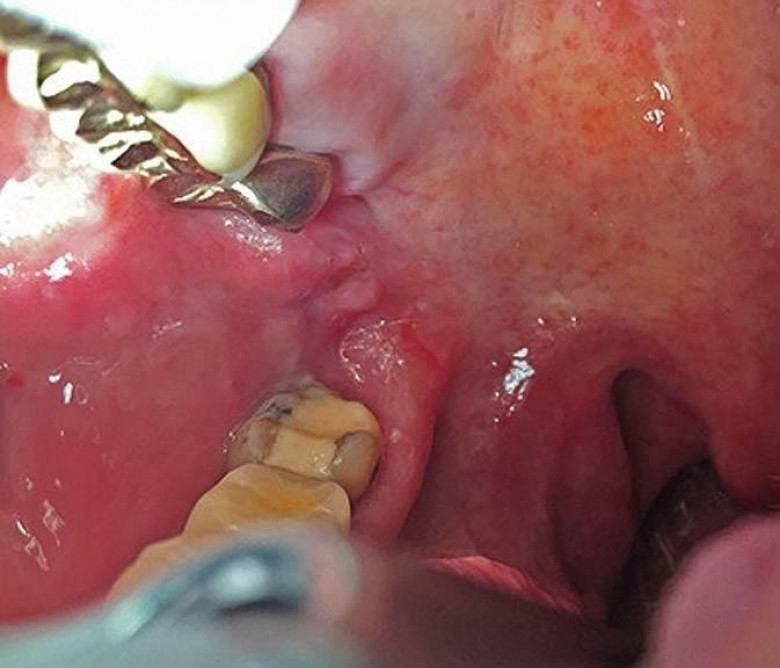

65-ամյա կնոջ լնդի միջից դուրս բերածը շոկի մեջ գցեց բժիշկներին (լուսանկարներ 16+)

Համբուրգի 65-ամյա բնակչուհին դիմեց բժիշկներին, ասելով, որ չի կարողանում գտնել ատամները լվանալու ժամանակ կորցրած էլէկտրական խոզանակի կտորը: Բժիշկները նախ հետազոտեցին կնոջ ստամոքսն ու աղիները, բայց ոչինչ չհայտնաբերեցին և նրան ուղարկեցին տուն: Բայց մի քանի օր անց կինը կրկին դիմեց հիվանդանոց՝ գանգատվելով, որ ոչինչ չի կարողանում ոչինչ ուտել: Դիմածնոտային վիրաբույժը կնոջ բերանի խոռոչի փափուկ հյուսվածքներում 6 սմ երկարությամբ օտար առարկա նկատեց: Պարզվեց, որ դա հենց ատամի խոզանակի ջարդված կտորն էր: Վիրահատությունից հետո մի քանի օր անց կինը դուրս գրվեց: